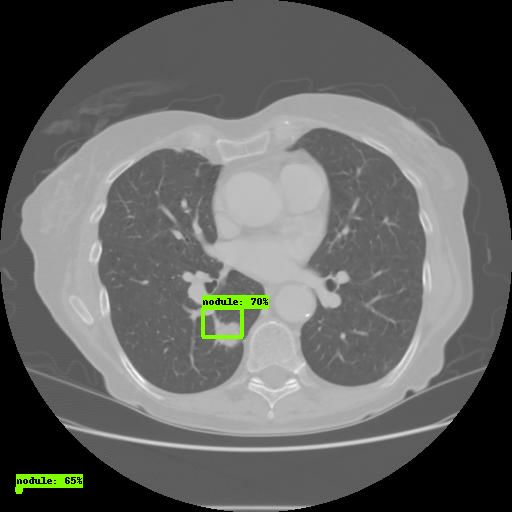

比如,人工智能诊断工具可以从医学影像中识别人眼看不见,或者容易看漏的病灶。在这方面,根据CT影像识别肺结节筛查肺癌,是目前最常见的应用之一。

►利用机器学习,识别肺结节。图片来源:Vatsal Sodha, Medium